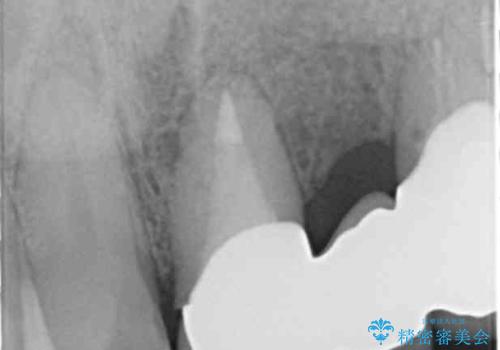

- ブリッジの支台歯であった左上の犬歯が折れたことを主訴に来院された患者様です。

犬歯は歯ぐきの奥深くまで割れており保存不可能な状態でしたが、どうしても抜きたくないとのことでした。

歯を牽引し健全歯質を歯肉縁上まで引き上げ、歯の保存を試みることにしました。

歯の牽引後、ブリッジの仮歯で保定しながら歯肉・骨の治癒を待ったのち、ブリッジによる補綴を行いました。

根の長さが短くなるためブリッジの支台歯としては弱いこと、長期的予後は不明なことをご理解頂いた上で治療を行いました。

牽引により歯の保存が可能となり、ブリッジによる補綴を行うことができました。

健全歯質を歯肉縁上に出すためにしっかり挺出させたことで歯根長が短くなりましたが、仮歯で十分に保定した結果動揺度Ⅰ程度となり、ブリッジの支台歯にすることが可能と判断しました。